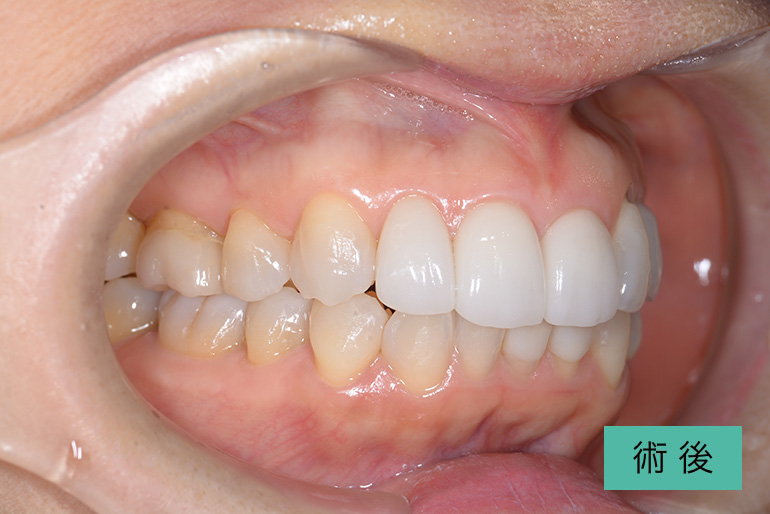

オールセラミック②

| 治療内容 | 上顎前歯右上3番から左上3番のセラミック冠 |

| 治療期間・回数 | 約1ヶ月、3回 |

| 費用(税込) | ¥990,000(165,000/1本)(補綴費用) ※自由診療 |

| リスク・副作用 | 疼痛、補綴物の脱落、咬合違和感、破折 |